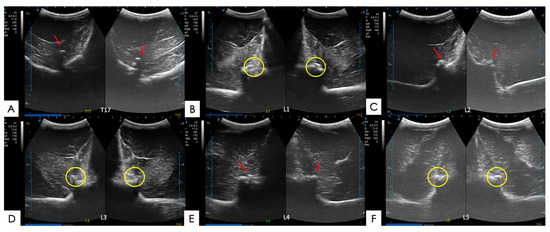

2.5.1. Articular Processes and Epaxial Muscle

2.5.2. Spinous Processes and Supraspinous Ligament